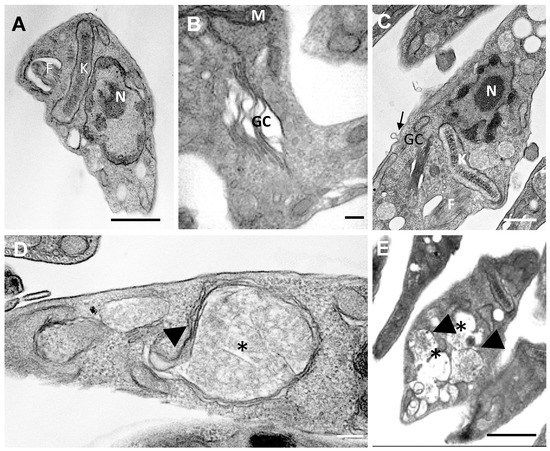

3.2.9. Electron Microscopy

Transmission Electron Microscopy